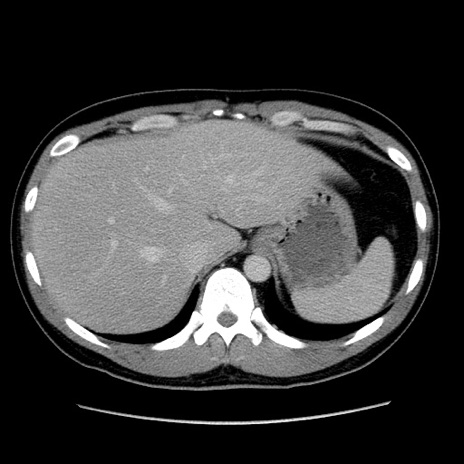

症例4(横断像)

【症例】30歳代男性

【主訴】腹痛、嘔吐

【現病歴】昨晩から突然の腹痛あり、その後嘔吐、軟便も出現。腹痛が改善しないため救急搬送となる。2日前にしめ鯖の食事歴あり。

【身体所見】意識清明、苦悶様、BP 135/90mmHg、BT 35.7℃、腹部:平坦、やや硬、心窩部〜臍部に自発痛、圧痛あり、筋性防御+、反跳痛-

【データ】WBC 8100、CRP 0.57